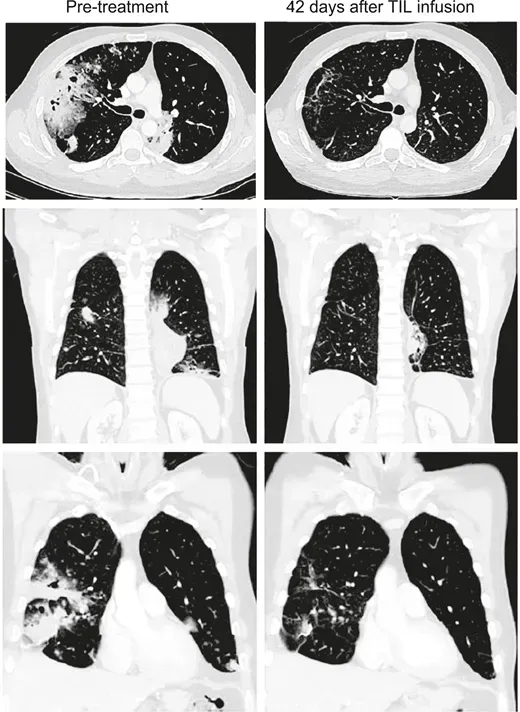

此外,《癌症探索》杂志曾报道一则经典案例,进一步证实其在肺癌治疗中的有效性:一名41岁IV期粘液性肺腺癌男性患者,携带KRAS G12D突变、肿瘤突变负荷(TMB)3.3mut/Mb、PD-L1表达0%,接受Lifileucel治疗前,治疗反应持续时间仅1.1+个月;治疗6周后,反应持续时间延长至26.2+个月,且疗效随时间加深,输注12周时部分缓解(PR)率高达81%(详见下图)。

▲图源“Cancer Discov”,版权归原作者所有,如无意中侵犯了知识产权,请联系我们删除